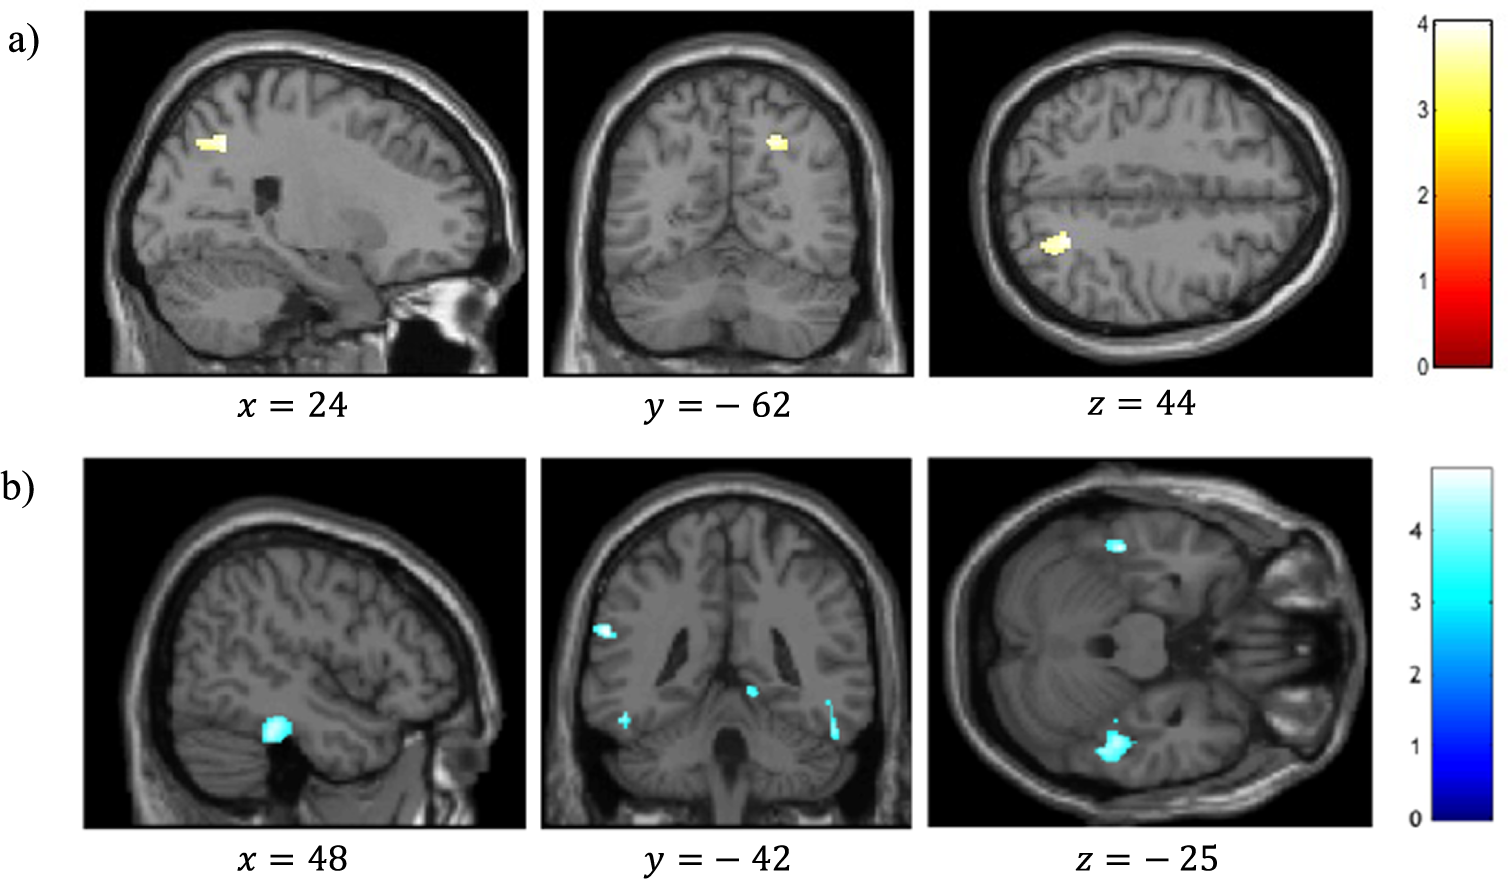

VBM analysis revealed a significant positive correlation between reality-monitoring accuracy and GMV in the right angular gyrus (peak MNI coordinates [23 −59 44], t = 4.03, p < 0.001; see Table 2 and Figure 3A).

Table 2. Clusters showing significant correlations between gray-matter volume and reality-monitoring measures (n = 35).

Note: Statistical threshold of p < 0.001 at the peak-level and FDR-corrected p < 0.05 at the cluster level.

Figure 3. Voxel-based morphometry analysis of correlation between gray-matter volumes and reality-monitoring performances, corrected for total intracranial volume and age (n = 35). Results are reported using z-values presented in the SPM canonical single subject template with MNI coordinates of the section. Regions that survived a statistical threshold of p < 0.001 at the peak-level (FDR-corrected p < 0.05 at the cluster level) are shown in (A) for positive correlation with reality-monitoring accuracy and (B) for negative correlation with externalization bias.

The analysis also revealed a significant negative correlation between the externalization bias and GMV in a cluster encompassing the left supramarginal gyrus and the left superior temporal gyrus ([−60 −42 24], t = 4.83, p < 0.001), in the right lingual gyrus ([15 −51 −3], t = 4.71, p < 0.001), and both in the left and the right inferior temporal gyrus and fusiform gyrus (respectively, [−46 −33 −26], t = 4.60, p < 0.001, and [48 −33 −24], t = 4.48, p < 0.001; Table 2 and Figure 3B).

Additional VBM analyses revealed a significant negative correlation between item memory and GMV in the right superior frontal gyrus (peak MNI coordinates [26 45 22], t = 4.57, p < 0.001; Table 2).

The present study sought to identify the neuroanatomical correlates of reality monitoring in a sample of schizophrenia patients with AHs. We reported two main findings: (a) the right hemisphere PCS length was positively correlated with reality-monitoring accuracy and negatively correlated with the externalization bias, that is, the misattribution of imagined words to an external source, and (b) the reality-monitoring accuracy was positively correlated with the GMV in the right angular gyrus, whereas the externalization bias was negatively correlated with the GMV in a set of temporal and parietal areas.

As we hypothesized, most of the regions for which the GMV correlated with reality-monitoring performances correspond to the temporoparietal areas previously identified by functional imaging during reality-monitoring tasks. We found several brain structures whose GMVs negatively correlate with the externalization bias, indicating that schizophrenia patients with AHs with reduced GMV in these structures are more likely to misattribute internally generated information to an external source.

First, we observed a negative correlation between the externalization bias and a cluster encompassing the left supramarginal gyrus and the left superior temporal gyrus, which is considered as a part of Wernicke’s area (BA 40) involved in auditory and speech processing. Disruption to this system would induce an inadequate treatment of the verbal items presented in reality-monitoring tasks and participate to patients’ misattributions of source. In addition, a recent meta-analysis on motor agency specifically highlighted the left BA 40 as an integral part of the body-ownership network [Reference Seghezzi, Giannini and Zapparoli44]. This cluster can thus be considered as an element of both verbal and nonverbal self-production recognition, suggesting its modality-general implication in reality-monitoring processes. Consistently, the GMV and activity of this temporoparietal region have also been associated with AHs in schizophrenia patients [Reference Modinos, Costafreda, van Tol, McGuire, Aleman and Allen45–Reference Zmigrod, Garrison, Carr and Simons47]. The causal implication of temporoparietal regions in reality monitoring has finally been demonstrated by noninvasive stimulation over this region that modulated the externalization bias in both healthy subjects and schizophrenia patients and alleviated AHs in schizophrenia patients [Reference Mondino, Poulet, Suaud-Chagny and Brunelin16, Reference Brunelin, Poulet, Bediou, Kallel, Dalery and D’amato48–Reference Otani, Shiozawa, Cordeiro and Uchida50].

The VBM analysis also revealed negative correlations between the externalization bias and gray matter in several posteroinferior temporal regions. Considered as associative visual areas, these structures have mainly been associated with visual processing and visual hallucinations [Reference Zmigrod, Garrison, Carr and Simons47,Reference Rollins, Garrison, Simons, Rowe, O’Callaghan and Murray51,Reference Stephan-Otto, Siddi, Senior, Muñoz-Samons, Ochoa and Sánchez-Laforga52]. For now, the implications of the correlation between their GMV and externalization bias in our semantic task are unclear, and future studies should clarify the relationship between reduced GMV in these areas and the incorrect source attributions observed in schizophrenia patients with AHs. However, a substantial body of functional studies has already reported an activation of the right lingual gyrus during Theory-of-Mind tasks, involving among other things to make the distinction between internal and external space [Reference Jáni and Kašpárek53]. On its side, the left inferior temporal gyrus has been shown to specifically activate in the reality-monitoring contrast “correct attributions” versus “misattributions” in healthy participants [Reference Kensinger and Schacter54].

We identified a significant positive correlation between the reality-monitoring accuracy and the GMV of the right angular gyrus. This result replicates in a population of schizophrenia patients with AHs the results reported by Buda et al. [Reference Buda, Fornito, Bergström and Simons23] in a sample of healthy subjects. The right angular gyrus is engaged in a wide range of tasks reflecting our ability to discriminate the internal from external environment, such as Theory-of-Mind or agency attribution tasks [Reference Mar55,Reference Sperduti, Delaveau, Fossati and Nadel56]. Moreover, several case reports described its causal involvement in out-of-body experiences, a phenomenon referring to an autoscopic experience during which the subject perceive the world from an out-of-body position [Reference Blanke, Ortigue, Landis and Seeck57,Reference De Ridder, Van Laere, Dupont, Menovsky and Van de Heyning58]. In this way, our findings contribute to define the right angular gyrus as a pivotal neural locus for the distinction between the self and the external world. Its increased GMV may underlie its overactivity and in turn sustain decreased reality-monitoring performances in schizophrenia patients with AHs.